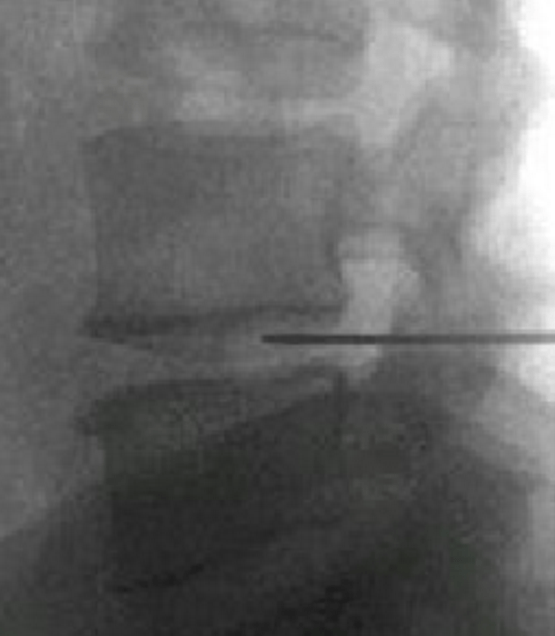

頸、腰椎間盤射頻微創(chuàng)手術

經過多年的發(fā)展,現在的延安大學咸陽醫(yī)院疼痛科在診療技術上已經達到一流的水平。尤其在頸、腰椎間盤突出微創(chuàng)治療方面,手術量居地區(qū)前列,脊柱壓縮骨折椎體成型術、頸、腰交感神經射頻調控微創(chuàng)手術、三叉神經痛、帶狀皰疹后神經痛以及外周血管介入、腫瘤微創(chuàng)介入、內臟出血等介入治療方面,為地區(qū)最優(yōu)秀的疼痛科之一。